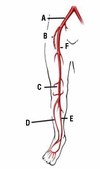

The picture shows arterial supply of the upper limbs, what is A?

Radial artery

The picture shows arterial supply of the upper limbs, what is B?

Brachial artery

The picture shows arterial supply of the upper limbs, what is C?

Subclavian artery

The picture shows arterial supply of the upper limbs, what is D?

Ulnar artery

The picture shows arterial supply of the upper limbs, what is

Axillary artery

What is A?

External iliac artery

What is B?

Deep femoral artery

What is C?

Popliteal artery

What is D?

Anterior tibial artery

What is E?

Posterior tibial

What is F?

Superficial femoral

What artery is the femoral artery a distal continuation of?

External iliac artery

Where does the poplital artery branch into the anterior and posterior tibial artery?

Poplital fossa

What is the complete branching of the common iliac artery?

Common iliac - external iliac (internal iliac) - superficial femoral (deep femoral) - popliteal - anterior tibial (posterior tibial) - dorsalis pedis

What is the complete branching of the subclavian artery?

Subclavian - axillary - brachial - radial and ulnar